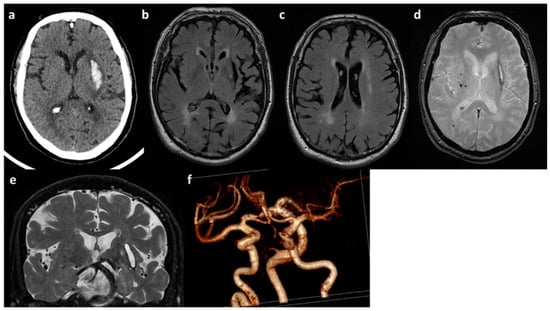

2.3. Peripheral Blood Type I Interferon Activity

In order to gain insight into a possible inflammatory mechanism underlying the patients’ phenotypes, we determined their peripheral blood type-I IFN score (IS), which reliably tests positive in AGS1 patients [25]. We identified a negative IS for patient A (data not shown) and moderately positive IS for patient B (Figure 3) (IS = 0.93, normal values < 0.7). We note that certain gene scores have high leverage (IFI27) in the overall IS, whereas others showed more minor (ISG15, SIGLEC1) or negligible (IFI44, IFIT1, RSAD2) change.

Figure 3.

Peripheral blood type I interferon signature of patient B. The panel shows the expression of six type I-IFN stimulated genes, indicated in the X axis. Red bars indicate expression levels in patient B; black bars represent the average of twenty healthy donors. Interferon score (FI) is indicated in the legend.